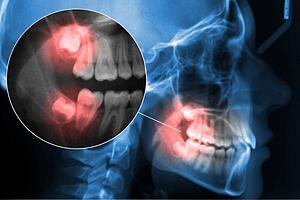

Why do wisdom teeth cause so many problems? Wisdom teeth or third molars usually erupt between the ages of 17 and 25, a time when there is often insufficient space in the mouth, and when this happens, the teeth can grow in crooked, become partially impacted or press into the mouth.